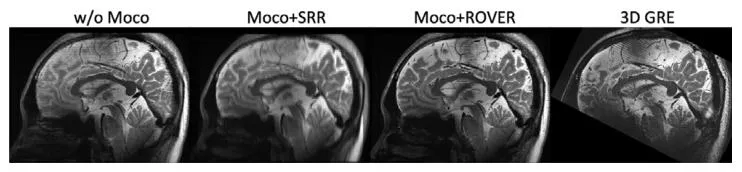

Fig. 12. Comparison of in-vivo human brain reconstruction results acquired at 7T MRI without motion correction (w/o Moco), with motioncorrected LS-SRR (Moco+SRR), and motion-corrected ROVER-MRI reconstruction (Moco+ROVER), benchmarked against a high-quality reference 3Dgradient echo (3D GRE) image

图 12 7T磁共振成像(MRI)采集的人类在体脑部重建结果对比:无运动校正(w/o Moco)、运动校正后的最小二乘超分辨率重建(Moco+SRR)及运动校正ROVER-MRI重建(Moco+ROVER),以高质量参考3D梯度回波(3D GRE)图像为基准进行评估。